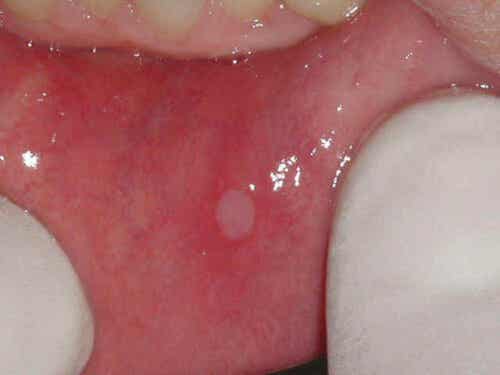

Suun haavaumat ovat yleensä muodoltaan pyöreitä ja valkeita vaurioita, joita ympäröi tulehtunut alue. Ne ovat normaalisti melko pieniä kooltaan.

Kipeitä haavaumia voi olla samaan aikaan useampi kuin yksi. On myös tapauksia, joissa nämä suun vauriot ovat melko suuria, jolloin myös paraneminen on monimutkaisempaa.